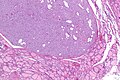

- Discrete lesion with adipose tissue with in the thyroid gland.